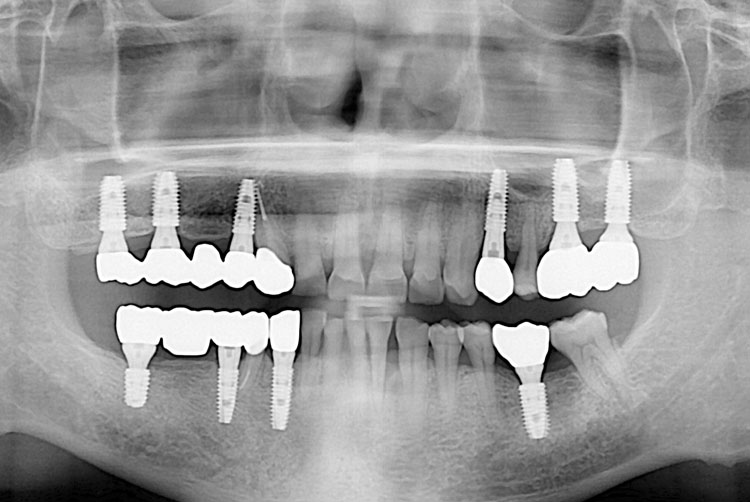

[임플란트] 임플란트

치료전 : 2016-02-17

치료후 : 2020-01-08

세종치과는 많은 환자와 다양한 케이스를 바탕으로 항상 편안한 임플란트 수술을 제공하고자 노력하고,

오래동안 튼튼히 쓸 수 있는 임플란트 수술을 가장 큰 목표로 삼고 있습니다